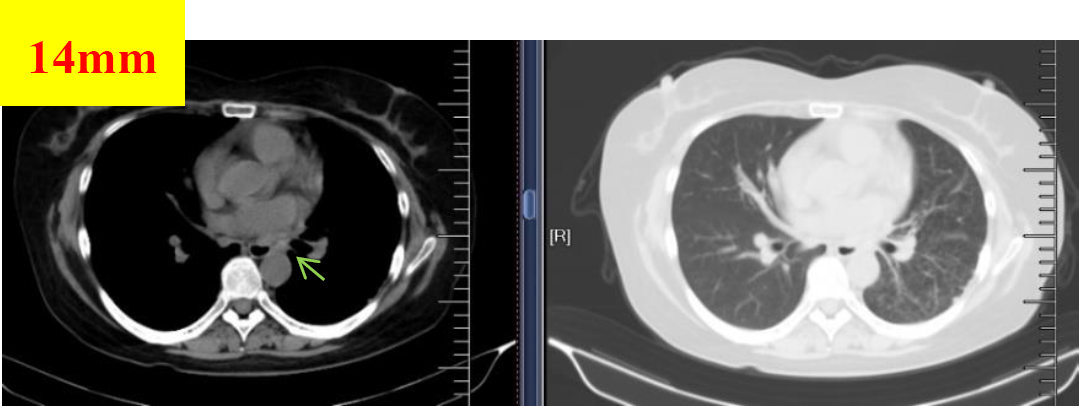

图1 2018.06.19基线检查

图2 2018.07.23影像学检查(PR)